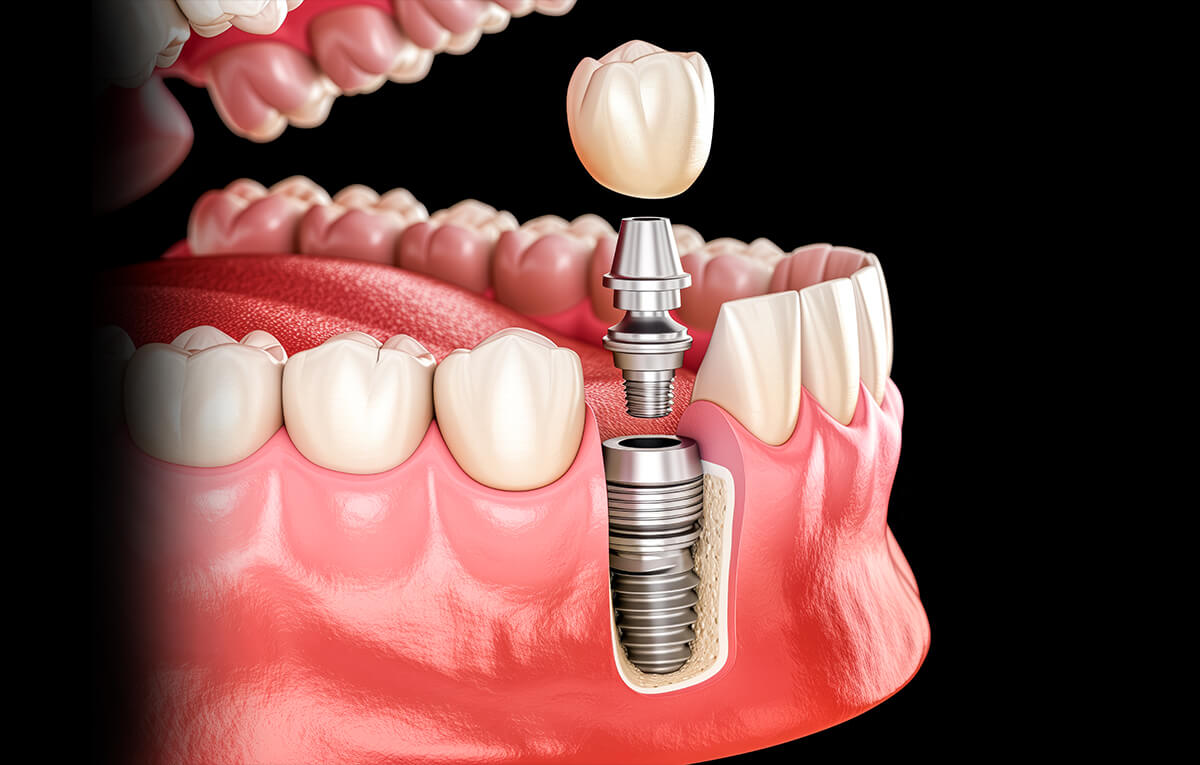

Uma raiz artificial, geralmente de titânio, que é cirurgicamente inserida no osso do maxilar ou mandíbula.